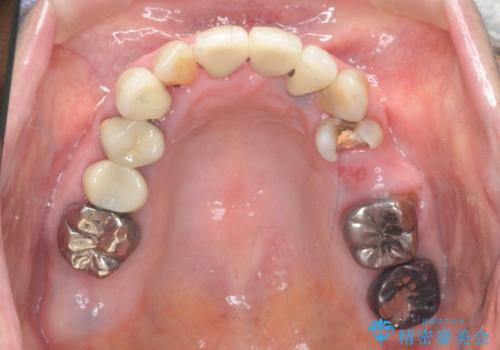

- 見た目の悪い銀歯や虫歯、歯の欠損、全体的な治療を希望されて来院されました。

インプラント治療や根管治療・セラミック治療を総合的に考えた精度の高い治療を計画し、しっかり噛めるようになるのはもちろん長期的な予後や審美性の向上を考えた全顎的な治療を実践していきます。